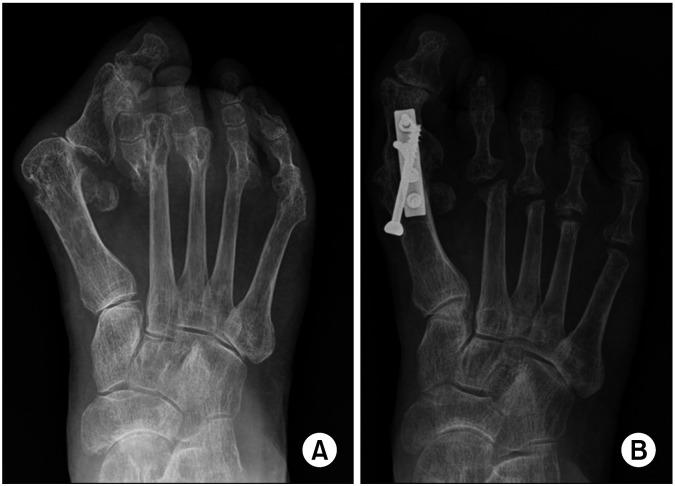

To study the clinical and radiologic factors related with overall patient satisfaction of joint scarifying reconstruction on severe rheumatoid forefoot deformity (RFD).

Forty cases of RFD were retrospectively enrolled. A questionnaire on the factors for patient's expectations and satisfactions of the greater and lesser toes was administered, including repression of relapse in deformity (D), pain reduction (P), improvement in shoe wearing (S), barefoot activity (B), and appearance (A). Overall satisfaction were assessed using the 5-digit-scale. Hallux valgus angle, 1, 2 intermetatarsal angle, and other radiologic parameters were measured. Pearson's correlation and multiple linear regression analyses were used to evaluate the relationships between these factors and overall satisfaction.

Overall satisfaction was 4.0±0.82. Postoperative radiologic parameters were corrected in adequate range. Visual analog scale (VAS) was reduced from 7.2±2.1 to 2.2±1.8. For the greater toe, patient's expectations (D, P, S, B, and A) were 4.2, 4.1, 3.0, 2.5, 2.7 and satisfactions were 4.2, 4.0, 3.4, 3.5, 3.3, respectively. For the lesser toes, patient's expectations (D, P, S, B, and A) were 3.9, 4.1, 3.4, 3.0, 2.8, and satisfactions were 3.4, 4.0, 3.4, 3.6, 2.9, respectively. Satisfactions with P and B, and reduction amounts of VAS were significantly correlated with overall satisfaction.

研究与严重类风湿性前足畸形(RFD)关节切除重建患者总体满意度相关的临床和放射学因素。

回顾性纳入40例RFD患者。发放一份关于患者对拇趾和小趾的期望及满意度因素的问卷,包括畸形复发抑制(D)、疼痛减轻(P)、穿鞋改善(S)、赤足活动(B)和外观(A)。采用5分制评估总体满意度。测量拇外翻角、第1、2跖骨间角及其他放射学参数。采用Pearson相关性分析和多元线性回归分析评估这些因素与总体满意度之间的关系。

总体满意度为4.0±0.82。术后放射学参数在适当范围内得到矫正。视觉模拟评分(VAS)从7.2±2.1降至2.2±1.8。对于拇趾,患者的期望(D、P、S、B和A)分别为4.2、4.1、3.0、2.5、2.7,满意度分别为4.2、4.0、3.4、3.5、3.3。对于小趾,患者的期望(D、P、S、B和A)分别为3.9、4.1、3.4、3.0、2.8,满意度分别为3.4、4.0、3.4、3.6、2.9。对P和B的满意度以及VAS降低量与总体满意度显著相关。